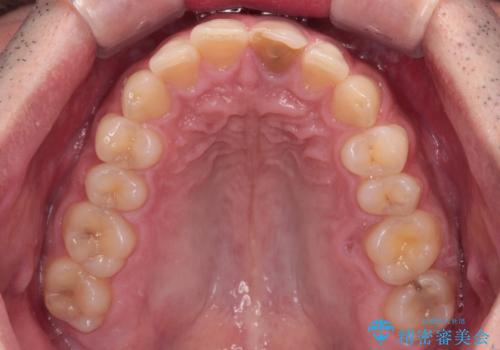

- 神経を取り除いたことで変色した前歯を気にして来院された患者様です。

根管治療はやり直さずに、ファイバーポストを使用した土台を植立してオールセラミッククラウンにて補綴することとしました。